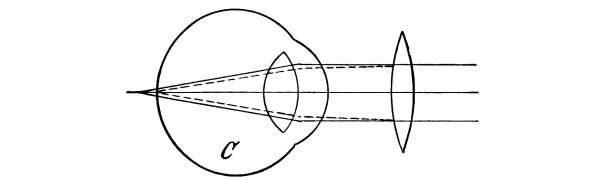

The Nose, 57—The Sense of Smell, 58—The Mouth, 59—The Hyoid Bone, 60—The Teeth, 60—The Sense of Taste, 61—Salivary Glands, 61—The Tonsils, 62—The Ear, 63—Eustachian Tubes, 63—Sensation of Hearing, 65—The Eye, 66—Lachrymal Gland, 68—Coats of the Eye, 68—Light Rays and Sight, 70—Accommodation, 72—Color Perception, 73. |